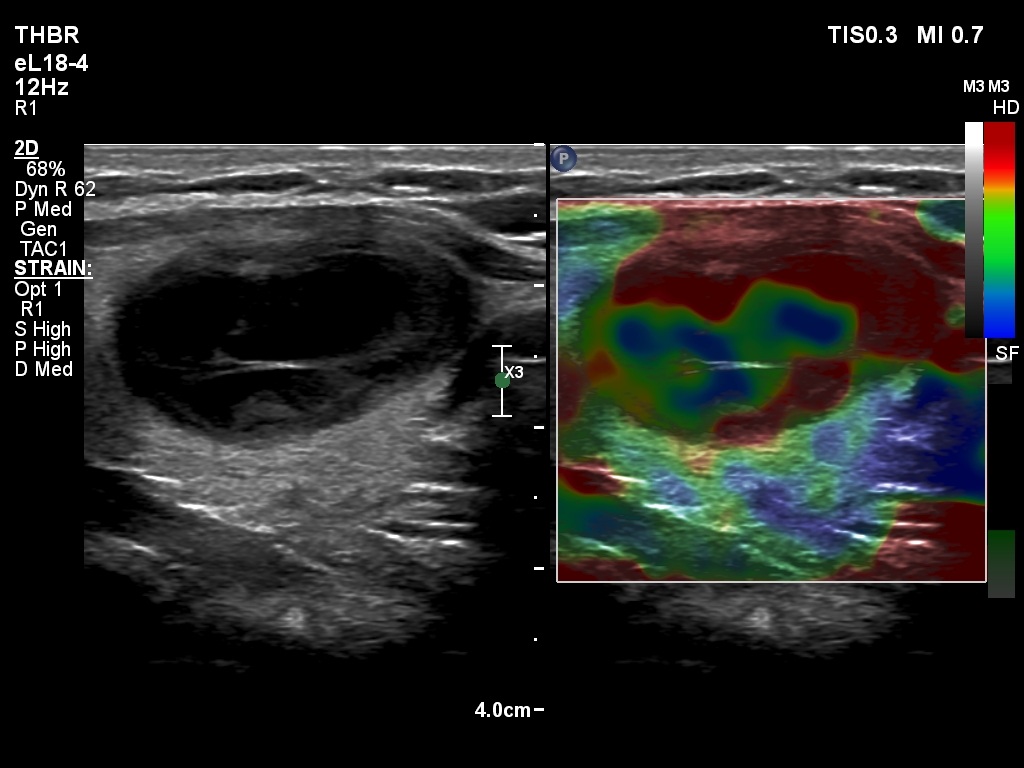

Five months after the first examination (third row of images)

Clinical presentation: The patient had no complaints. She was referred for evaluation of an elevated TSH level.

Palpation: no abnormality.

Laboratory tests: 4.76 mIU/L, aTPO 0,6 U/mL.

Ultrasonography. The thyroid was echonormal. There was a hypoechoic nodule in the ventral part of the left lobe. The ventral borders of the lesion were undefined because the echogenicity of the lesion and the neighboring strap muscle was identical.Suggestion: TSH in a year, ultrasound in two years, in the event of complaints at once.

Comments.

- Compared with the nodule just after the aspiration with that seen five months later, a spontaneous further decrease can be observed.

- On the second examination, we cannot see cystic portions, therefore the intranodular echogenic figures might cause concern. However, if we take the ultrasound pattern at the previous examination into account, this concern is not justified.

- The presentation of the nodule at the follow-up is an example of non-pathological cause of blur.